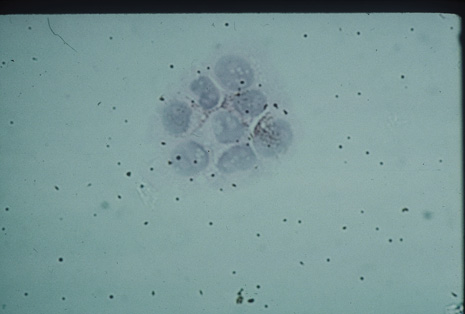

Although keratocentesis had been advocated historically as a treatment for active uveitis, it lost the attention of ophthalmologists until 1919, when Bruckner3 first examined the aqueous humor for diagnostic purposes. Laboratory techniques were revolutionized in the 20th century in areas such as: (a) evaluating very small aliquots of fluid (0.2 to 0.3 mL of aqueous or vitreous), and (b) identifying specific microbial organisms and the predominance of other cell types, antibodies, and proteins in these fluids (Figs. 1, 2, 3, 4, 5, and 6). These advancements have led to the development of diagnostic paracentesis for sight-threatening ocular inflammations that are difficult to diagnose. Witmer4 and O'Connor5 have provided strong evidence that samples of the aqueous humor reflect the antibody-producing capabilities of the iris and ciliary body, particularly when more specific antibody per unit of gamma globulin can be found on the aqueous humor than in the blood of the same patient.6–8 These determinations may be highly significant when one considers the fact that diseased tissue is being bathed in an antibody-containing fluid that is elaborated locally. For instance, in the case shown in Figure 1, the immunofluorescent antibody titer to toxoplasmosis is four times greater in the vitreous aspirate at the time of vitrectomy for repair of retinal detachment than in the plasma. These same considerations have long been recognized in syphilis of the central nervous system, wherein specific antibodies may be present in the cerebrospinal fluid but not in the blood. This is also the case with an unusual presentation of ocular coccidioidomycosis9 or toxocariasis.

Many forms of uveitis are characterized by specific types of inflammatory cells. Usually, however, one encounters mixtures of cell types in any given specimen, with the relative percentages of lymphocytes and polymorphonuclear leukocytes varying. There may be unusual numbers of eosinophils, or macrophages laden with lens material may be present. Thus, an enumeration of the cells and a careful analysis of their structure can be useful as a diagnostic aid (Figs. 7, 8, 9, 10, 11, 12, 13, 14, 15, 16, 17, 18, 19, and 20). Figure 15 demonstrates eosinophils that were aspirated from the anterior chamber of a patient with Toxocara canis endophthalmitis. Figure 12 demonstrates malignant cell infiltrate from the vitreous, showing the stained presence of monoclonal light chains being elaborated in the cytoplasm. Interleukin-10, detectable in the vitreous of intraocular lymphoma patients, is also directly indicative of both the clinical activity and the number of malignant cells as observed by cytopathology.